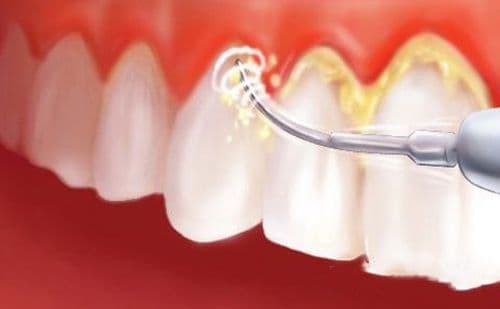

- Công nghệ cạo vôi răng tiên tiến nhanh chóng làm sạch các mảng bám chân răng đem lại hiệu quả tối ưu.

Để hỗ trợ thực hiện các dịch vụ khám bệnh răng miệng tổng quát và nha khoa thẩm mỹ, khoa Răng hàm mặt bệnh viện Thu Cúc đã trang bị các thiết bị y tế công nghệ cao hiện đại, được nhập khẩu từ nước ngoài như: hệ thống gồm 6 ghế máy nha khoa Gnatus (Braxin), đèn hàn quang trùng hợp Litesx (Mỹ), máy X quang kỹ thuật số RSV (Pháp), máy nội soi răng (Hàn Quốc),.. Với sự hỗ trợ của hệ thống trang thiết bị này, kỹ thuật cạo vôi răng tại bệnh viện Thu Cúc được thực hiện nhanh gọn và không ảnh hưởng đến răng, không gây cảm giác ê buốt, đau nhức răng cho người bệnh. Dưới sự hỗ trợ của các công cụ nha khoa và kinh nghiệm của bác sĩ, việc lấy cao răng chỉ mất khoảng thời gian ngắn mọi mảng bám quanh răng đều được loại bỏ hoàn toàn giúp bạn nhanh chóng phục hồi hàm răng chắc khỏe.

Quy trình cạo vôi răng được thực hiện bài bản theo đúng quy định tiêu chuẩn của Bộ Y tế. Theo đó, các nha sĩ thực hiện các thao tác một cách khéo léo, nhẹ nhàng giúp loại bỏ những mảng bám và vôi đã bám cứng trên răng, làm sạch những tác nhân viêm nhiễm nằm sâu dưới nướu lợi. Toàn bộ răng được làm sạch bởi máy cạo vôi răng bằng sóng siêu âm kết hợp với kĩ thuật đánh bóng và tạo cho răng có bề mặt mịn giảm thiểu các mảng bám và tác nhân gây bệnh răng miệng.